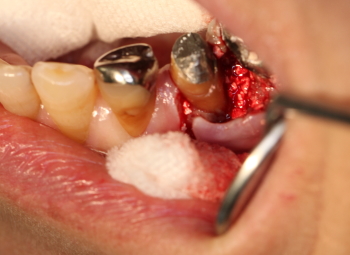

2016年04月06日

同部を剥離、掻爬

骨補填剤を充填。

縫合